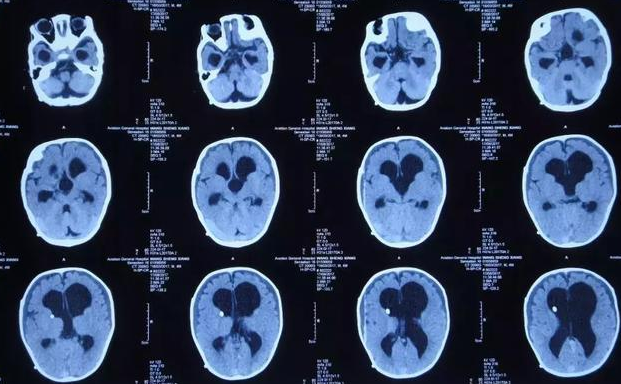

流行性脑膜炎的病徵包括发高烧、剧烈头痛、颈部僵硬及嗜睡,亦会有呕吐、畏光或皮疹等情况出现。若情况严重更可造成脑部损害或死亡。脑部损害可导致智力受影响、智力发展迟缓、失聪及电解质失衡。

不同个案的临床病徵可能并不一致。当细菌入侵血液(脑膜炎双球菌血症)或包围脑部及脊髓的内膜(流行性脑膜炎)时,可引致严重病症,病人须尽快接受抗生素治疗。